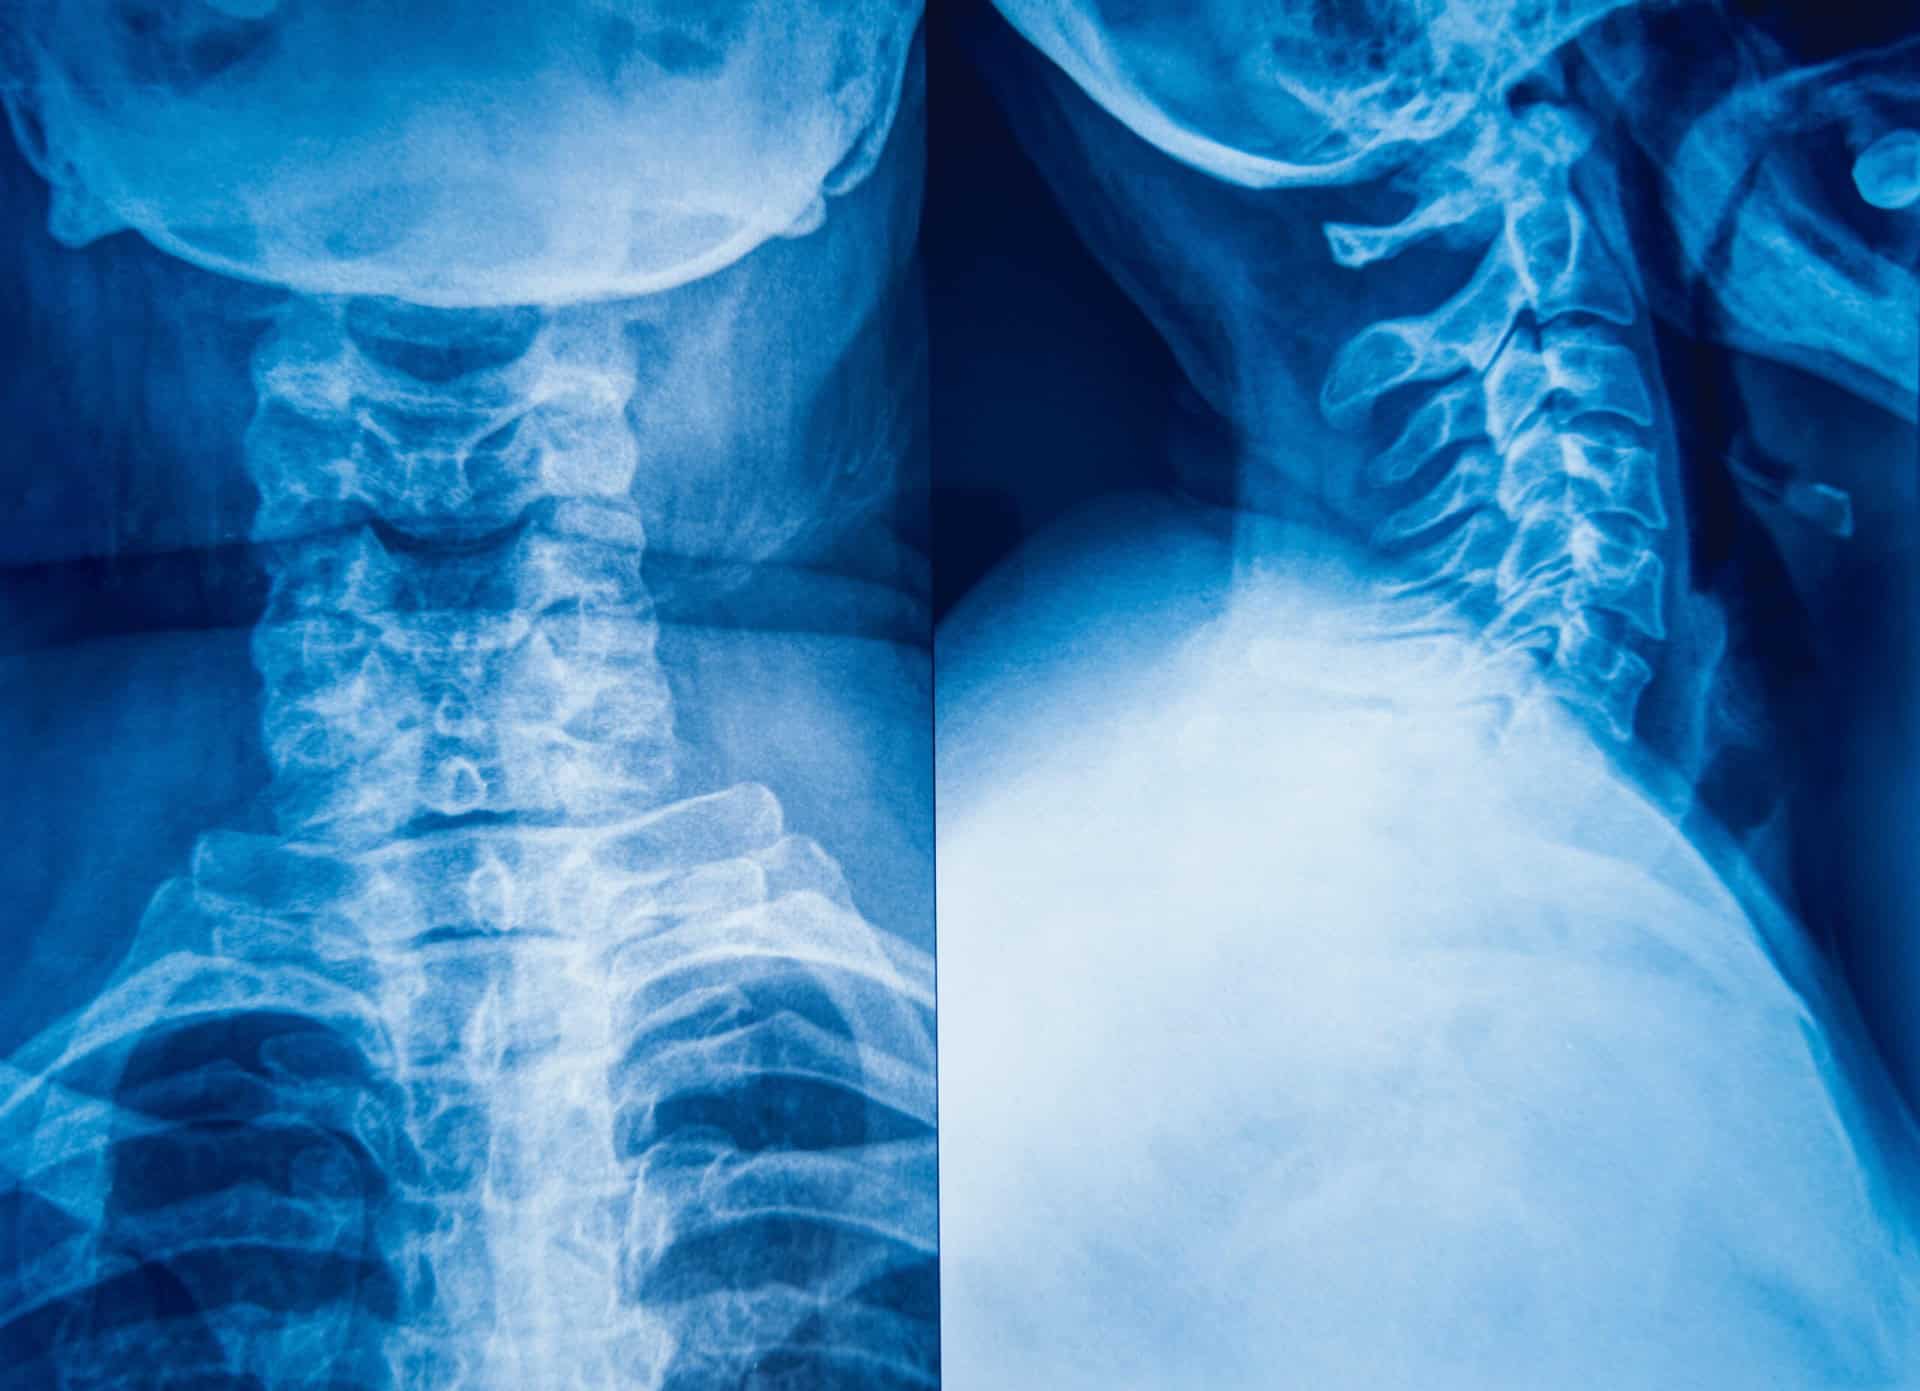

2. Spinal Cord Injury

Even minor spinal cord injuries come with serious long-term consequences. A motorcycle accident can cause a partial or complete tear of the spinal cord.

Depending on the severity of the injury, motorcyclists who suffer a spinal cord injury face partial or full paralysis.

The specific loss of function correlates with the part of the spine that is injured. Spinal cord injuries closest to the brain result in the most functional loss and typically lead to tetraplegia, which is full-body paralysis from the neck down.

11. Neck Injury

Even the safest bikers who always wear a helmet face the risk of neck injury during a motorcycle accident.

Neck injuries can hopefully be mild when they only impact the soft tissues in the neck area. Unfortunately, more often than not, motorcycle accidents lead to more severe neck injuries, such as broken neck vertebrae, nerve damage, or spinal cord damage in the neck area.